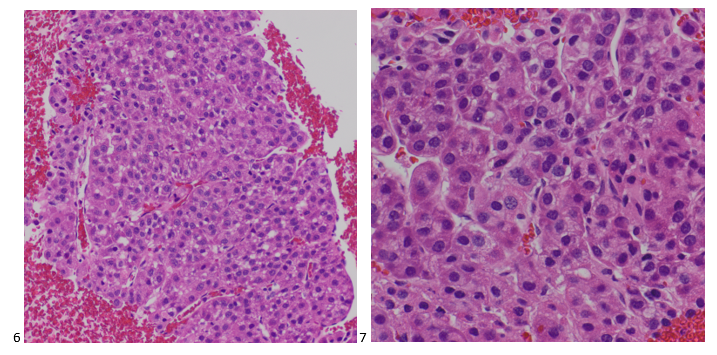

Case 2. Lung, Left Lower Lobe, CT-guided FNA

A 72-year old male with stage IIA squamous cell carcinoma underwent a VATS right upper lobectomy and mediastinal lymph node dissection. He completed adjuvant carboplatin/gemcitabine therapy. On a surveillance CT scan, the treated area demonstrated progression as well as multiple bilateral lung nodules. To determine whether the new left lower lobe superior segment lung nodule was a metastasis or new primary, a CT-guided biopsy was performed. The smears and cell block sections were negative for malignancy but demonstrated inflammatory cells and necrotic debris, consistent with a necrotizing inflammatory process (Images 3-5). A separate pass was sent for microbiological cultures to correlate our findings. The following day, Kinyoun and GMS stains were performed on paraffin-embedded sections of the cell block. No fungal organisms were identified on GMS, but acid-fast bacilli were noted by the cytologist on the Kinyoun-stained section (Image 6).

Diagnosis: Acid-fast bacilli (AFB), consistent with Mycobacterium Avium Complex. Isolated and confirmed by microbiology.